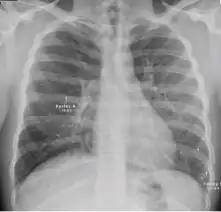

Dense homogenous opacity in right, middle and lower lobe of primary pulmonary TB.

Chest x-ray showing patchy opacification on the upper right and mid-zone lung with fibrotic shadows, as well as bilateral hilar lymphadenopathy.